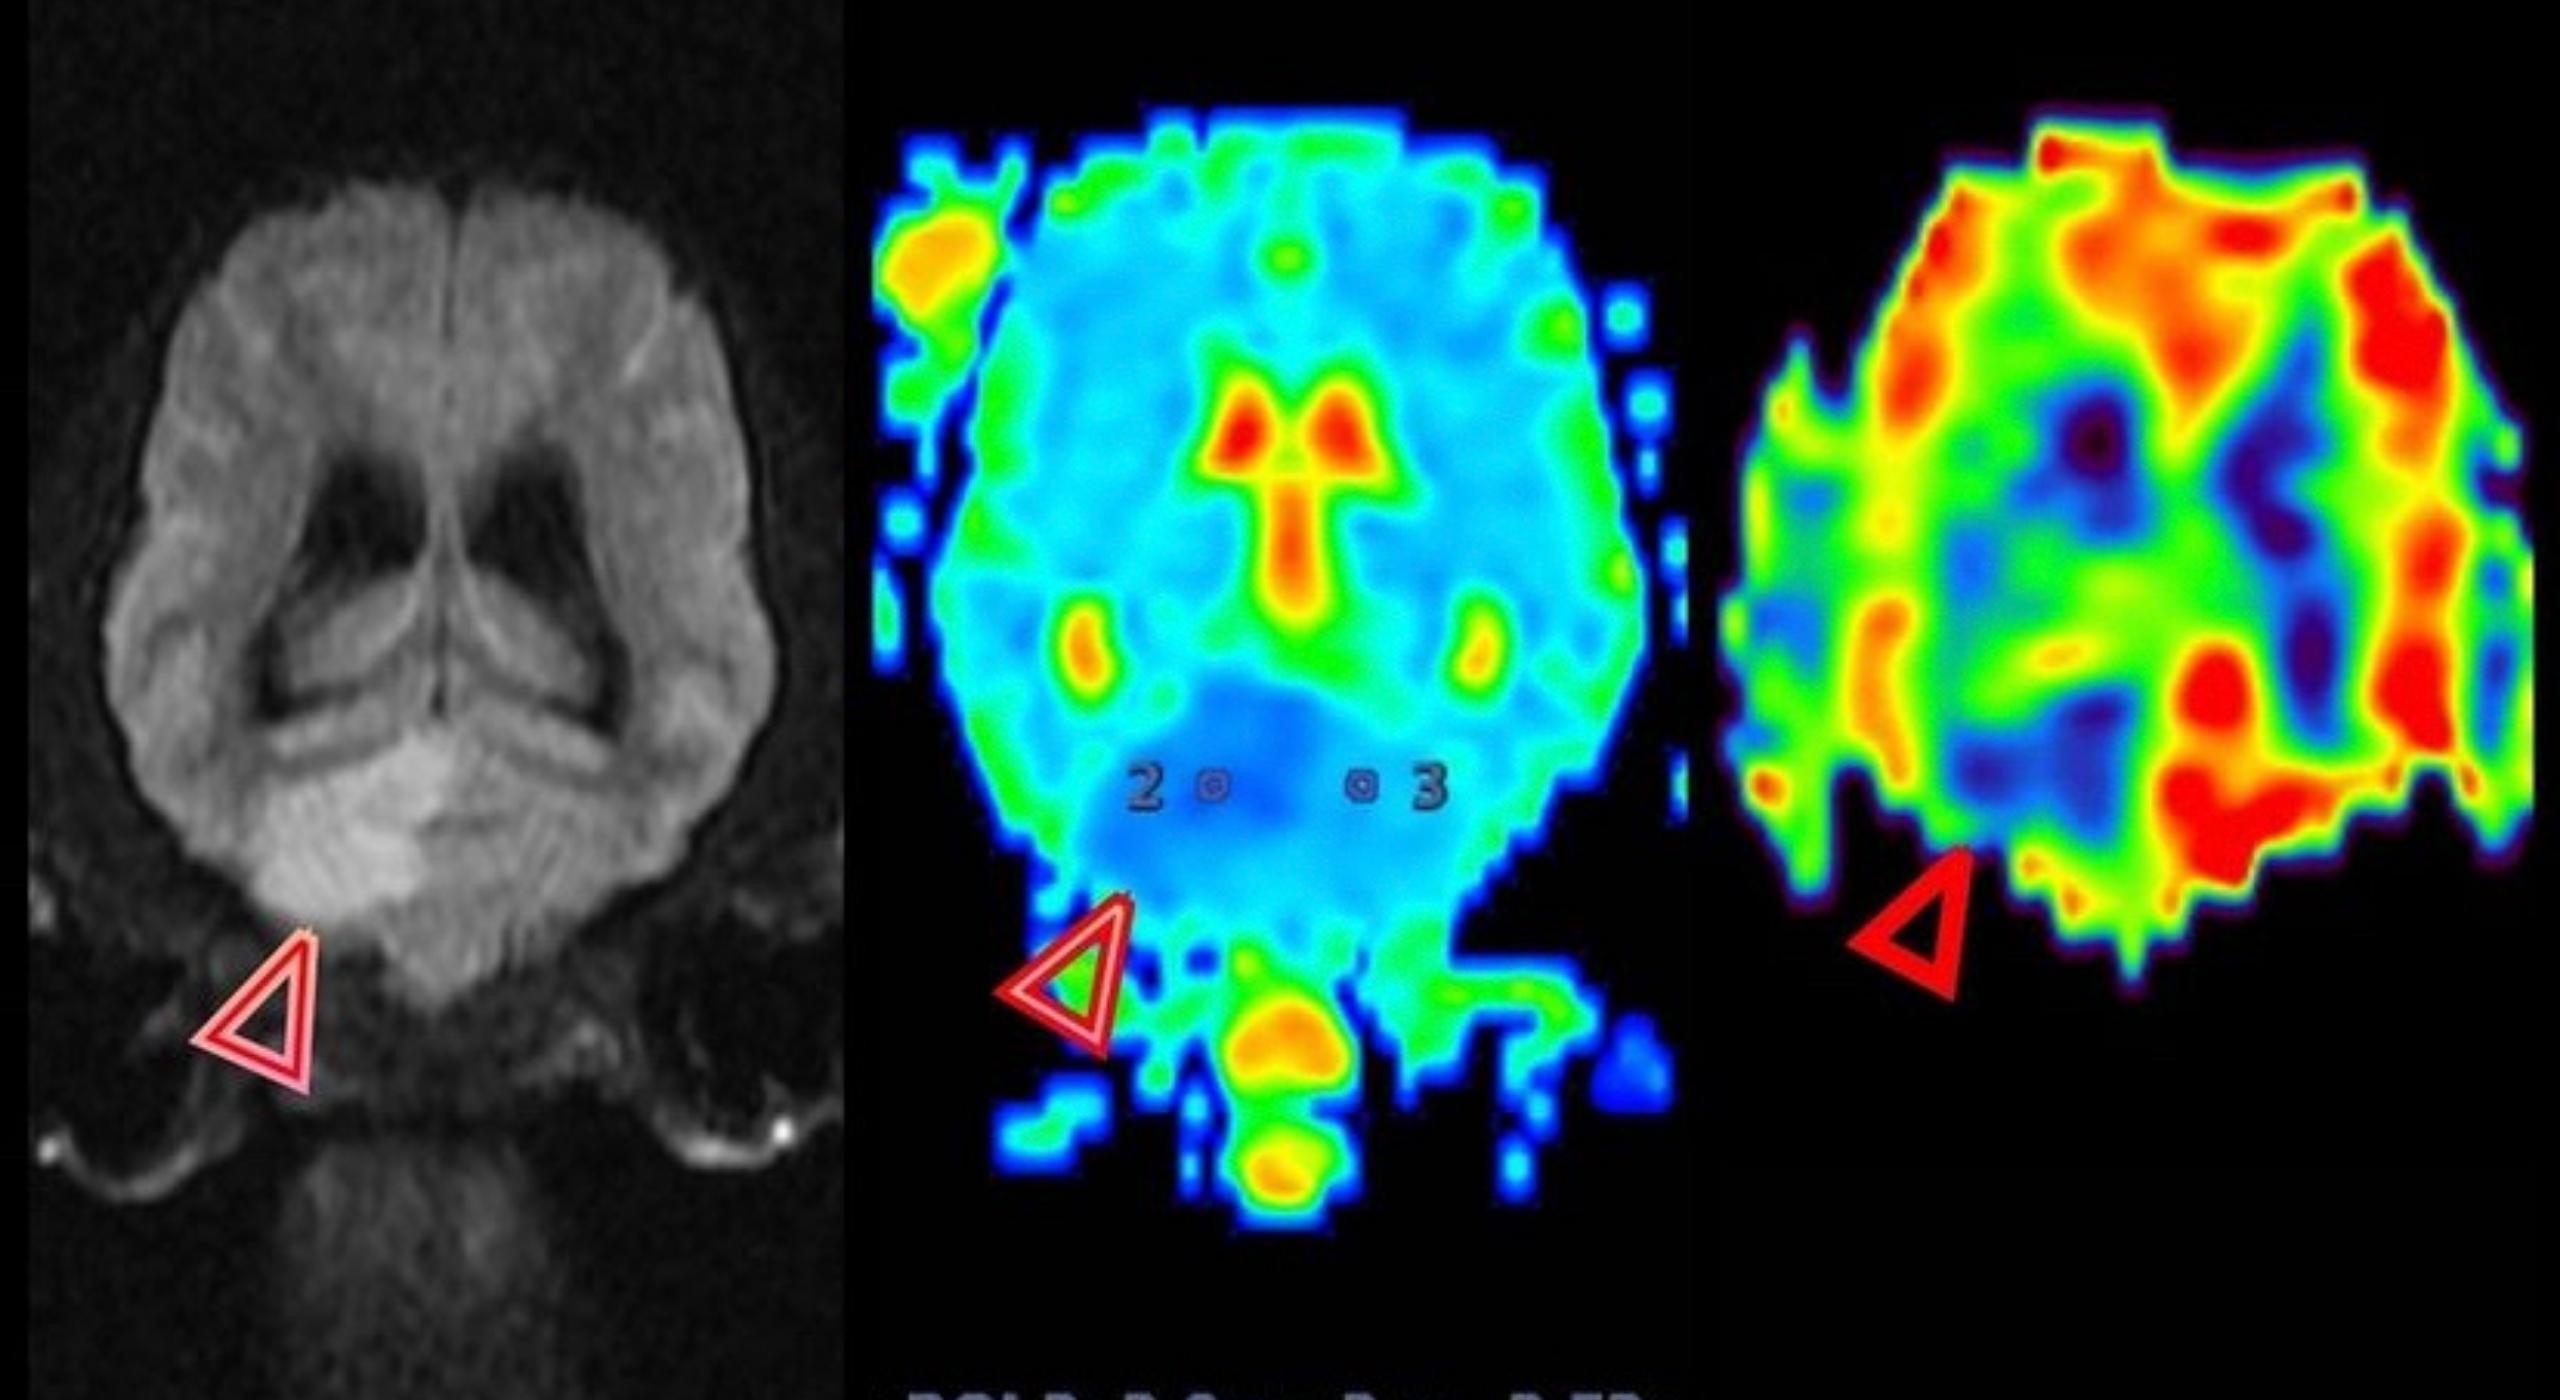

- Круглосуточная работа КТ и МРТ для животных.